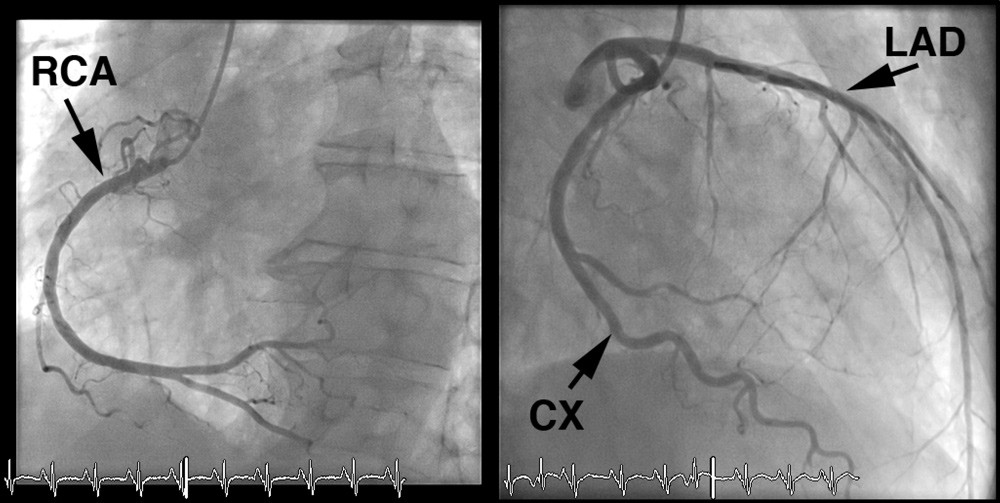

Pasienten hadde lav risikoprofil for koronarsykdom – han var til vanlig fysisk aktiv, var ikke-røyker, hadde ikke kjent diabetes, hypertensjon eller hyperkolesterolemi, og det var ingen familiær belastning for koronarsykdom. Koronar angiografi utført dagen etter overflyttingen viste mindre veggforandringer, men ingen signifikante stenoser (≥ 50 % reduksjon i karlumendiameter) i koronarkarene (fig 2).

Pasienten hadde utviklet en alvorlig hjertesvikt med symptomer i hvile – New York Heart Association (NYHA) klasse IV. Det var beskjedne funn ved koronar angiografi, og de kunne ikke forklare den betydelige reduksjonen i venstre ventrikkels funksjon. De regionale forskjellene i kontraktilitet passet heller ikke med takotsubokardiomyopati. EKG med ST-T-forandringer og høyt troponin I-nivå gjorde at man nå mistenkte myokarditt. Ticagrelor ble seponert, mens pasienten fortsatt fikk acetylsalisylsyre og statin på grunn av påviste veggforandringer i koronararteriene.